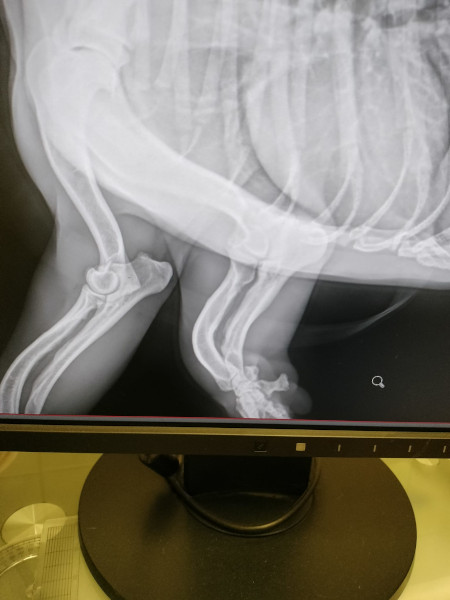

| Bemerkungen | Fehlstellung am Vorderbein |

Unsere Zuckerschnute Brikett wurde allein auf der Strasse gefunden und ins Tierheim Tamasi gebracht. Dort fiel sehr schnell auf, dass Brikett sein linkes Vorderbein nur eingeschränkt nutzen kann. Nach einer ausführlichen Untersuchung beim Tierarzt konnte festgestellt werden, dass der süsse Bub wahrscheinlich an Rachitis leidet. Vermutlich wurde im Welpenalter zu wenig auf hochwertige Ernährung und ausreichend Bewegung geachtet. Alle erforderlichen Vitamine und Nahrungsergänzungsmittel konnten gekauft werden, damit Brikett bald eine Besserung spürt. Brikett wird auf ca. 2 Jahre (Stand 04/2023) geschätzt und ist trotz seines derzeitigen Handicaps sehr verspielt, neugierig und menschenbezogen. Er zeigt sich flink und steckt voller Energie. Mit seinen Artgenossen und auch mit Kindern hat unser niedlicher Herzensbrecher keinerlei Probleme. Seine neuen Menschen sollten Freude daran haben, ihm alles liebevoll und geduldig beizubringen, was so ein Jungspund für sein weiteres Leben als Familienhund wissen muss. Ebenso sollten sich die neuen Besitzer bewusst sein, dass ein Hund nicht nur Freude, sondern auch jede Menge Arbeit und Verantwortung mit sich bringt, damit er sich zu einem tollen Begleiter entwickeln kann. Für unseren lustigen und cleveren Brikett suchen wir ein liebevolles und dauerhaftes Zuhause, wo er nebst viel Spass auch abwechslungsreiche Spaziergänge erleben darf, wo er artgerecht ausgelastet wird und täglich viel Liebe, Zeit und Aufmerksamkeit bekommt. Weiterhin sollte sein Beinchen nochmals tierärztlich kontrolliert werden, auch Physiotherapie würde sicherlich helfen. Brikett sucht also nach fürsorglichen Menschen, die seinen Heilungsprozess unterstützen und fortsetzen.